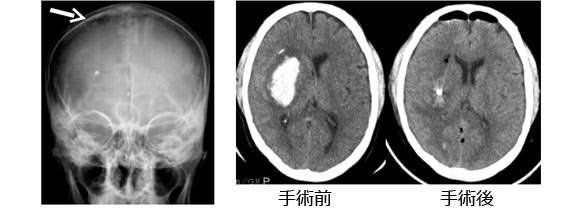

(1)穿頭手術

この方法は局所麻酔で行う手術方法です。出血がある部位の前頭部に1円玉程度の穴をあけて、脳の表面から血腫に向かって針を刺し、血腫を注射器などで吸引する方法です。手術時間は15-30分程度です。右の写真は53歳の患者さんで右脳出血です。右前頭部に穴をあけ て、チューブを挿入しています。左のCTが手術前で、右のCTが手術後です。血腫が十分とれているのがわかります。